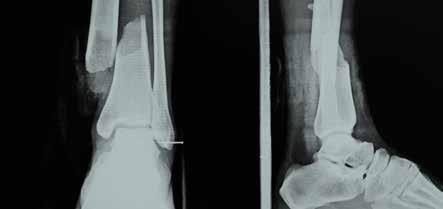

The X-ray showed a fracture in her leg.breuk dislocation